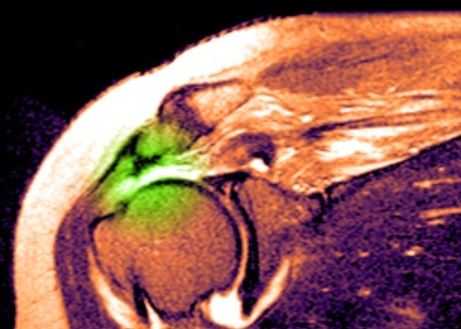

МРТ плечевого сустава. Т2-взвешенная корональная МРТ. Разрыв вращательной манжеты. Цветовая обработка изображения.

МРТ плечевого сустава. Корональные Т1-взвешенные МРТ. Переломы Хилла-Сакса и Банкарта.

Разрыв вращательной манжеты - также характерное повреждение области плеча - может быть связан как с травмой, так и дегенеративными процессами. Разрывы вращательной манжеты бывают полные и неполные. Кроме того, по МРТ плечевого сустава выделяют 3 градации, в основе которых лежит не только изменение сигнала на Т2-зависимых томограммах, но и морфологические изменения сухожилия.

МРТ. Корональная Т2-зависимая томограмма с подавлением сигнала от жира. Полный разрыв сухожилия надостной мышцы.

При МРТ плечевого сустава косвенным признаком разрыва вращательной манжеты служит высокий сигнал на Т2-взвешенных от поверхности сустава до субакромиальной (субдельтовидной) сумки. Частичные разрывы чаще всего по передней поверхности сухожилия м.supraspinatus, реже примыкая к большой бугристости или сухожилия м. infraspinatus.

МРТ плечевого сустава. Т2-взвешенная корональная МРТ. Субакромиальное скопление жидкости - косвенный признак разрыва вращательной манжеты.